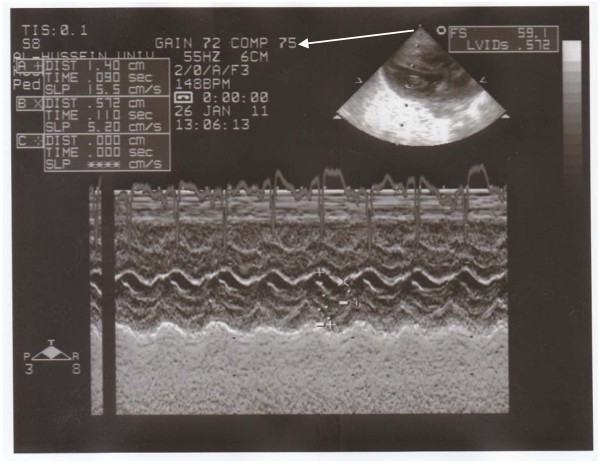

Neonatal echocardiography was performed during the first 3 days of life and cardiac measurements were determined by 2D and cross sectional M-mode echocardiography. Cardiac structure / function were assessed within the first three days of life by measuring left ventricle end-diastolic dimension (LVEDD), left ventricle end-systolic dimension (LVESD), ventricular septal thickness (VST), posterior wall thickness (PWT), percentage of ejection fraction (EF%) and percentage of shortening fraction (SF%).We used Hewlett Packard SONOS 5500 with a 5.0 or 3.5 MHZ transducer.

We found that the most common echocardiographic findings in IDMs were asymmetrical septal hypertrophy (80%), patent foramen ovale (PFO) (37.5%), and patent ductus arteriosus (PDA) (27.5%). We found a significant increase in left atrial thickness and interventricular septal dimension in infants of diabetic mothers in comparison to control (11.5 ± 1.8mm Vs 10.5 ± 0.9mm, and 5.0 ± 1.2mm Vs 4.0 ± 0.5mm respectively) (Table 4 & Figures 3,4,5). Cardiac TnI was significantly higher in IDMs with hypertrophic cardiomyopathy than without (median = 1.3 Vs 1.0 , P = 0.004** respectively) (Table 5).